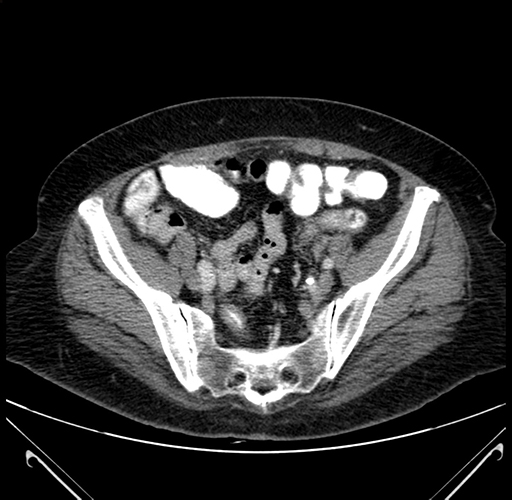

Pre-Chemo: Axial Venous